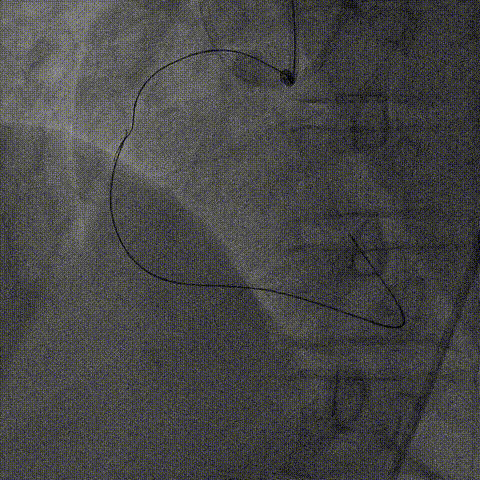

1、逆向导丝无法进一步前进突破后及时转换策略,决定以逆向导丝为路标,操控正向导丝定向穿刺逆向导丝。

2、正向升级为Gaia3导丝多投照体位穿刺并靠近逆向导丝,但无法进入远端真腔,升级为Pilot200导丝试图尽量考虑血管真腔加强支撑力后启动Reverse-Cart,多体位操控后导丝幸运进入血管远端真腔。